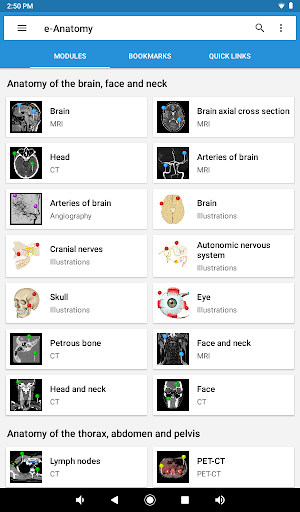

IMAIOS e-Anatomy adalah atlas anatomi manusia untuk dokter, ahli radiologi, mahasiswa kedokteran, dan teknisi radiologi. Dapatkan cuplikan lebih dari 26.000 gambar medis dan anatomi secara gratis sebelum berlangganan atlas anatomi manusia terperinci kami.

e-Anatomy didasarkan pada atlas daring IMAIOS e-Anatomy yang telah memenangkan penghargaan. Bawalah referensi anatomi manusia terlengkap, ke mana pun Anda pergi, di perangkat seluler atau tablet Anda.

e-Anatomy memiliki lebih dari 26.000 gambar yang berisi serangkaian gambar dalam tampilan aksial, koronal, dan sagital serta radiografi, angiografi, gambar diseksi, bagan anatomi, dan ilustrasi. Semua gambar medis diberi label dengan cermat, lebih dari 967.000 label tersedia dalam 12 bahasa termasuk Terminologia Anatomica Latin.

Baru : Sekarang Anda dapat memfilter modul berdasarkan wilayah atau jenis konten sehingga Anda dapat menemukan modul yang Anda cari lebih cepat.